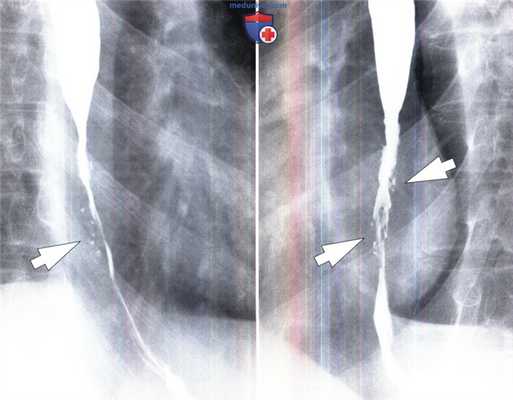

Герпетический эзофагит у мужчины 23 лет с нормальным иммунитетом. В дистальном отделе пищевода выявлены множественные точечные изъязвления (стрелки).

Эти проявления характерны для герпетического эзофагита у пациентов с нормальным иммунитетом.

Обратите внимание на диффузное сужение просвета в дистальном отделе пищевода, образующееся вследствие сопутствующего эозинофильного эзофагита.

Рефлюкс-эзофагит с сегментарным сужением просвета у мужчины 50 лет.

В дистальном отделе пищевода выявлено сегментарное сужение с ровными контурами без повреждений слизистой оболочки (без изъязвлений) (указатели).

Такие проявления более характерны для рефлюкс-эзофагита, чем для опухоли. Рефлюкс-эзофагит с сегментарным сужением просвета у мужчины 50 лет.